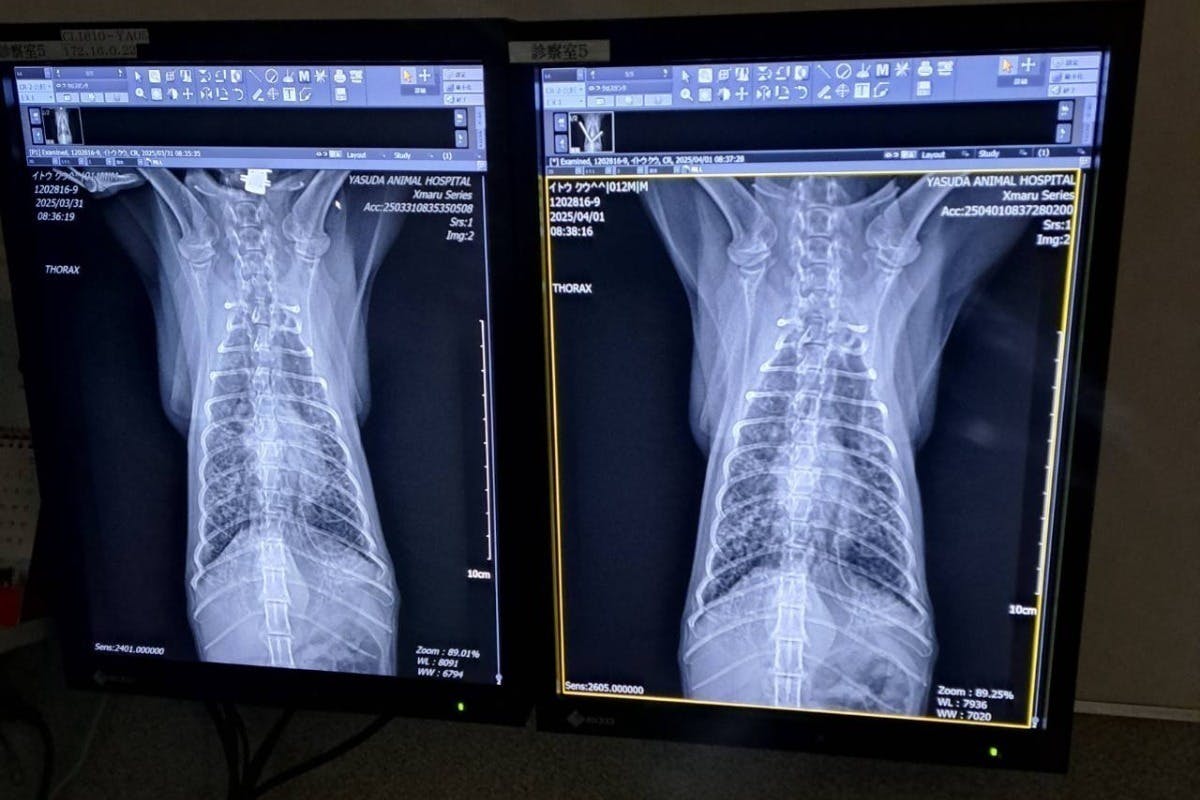

くうちゃん

昨年、突然の喘息を発症して重度の肺炎になり、酸素室のある病院に転院しました。

厳しい状態が続きましたが酸素室での治療の結果、今は元気に暮らしています。